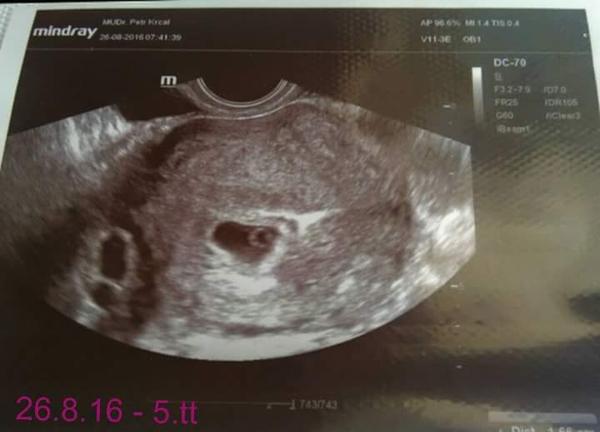

@zdenule23 tak já si nebyla jistá.já mela na utz naposledy tohle a to jsem byla v 5. týdnu s ms v 7.týdnu.

@zdenule23 v létě když jsem měla ZT tak to vypadalo v 5 týdnu takto a mělo to jen asi 6 mm, ted v 5.týdnu to má 2,4 cm a prý tehdy už bylo vidět, ze není něco v pořádku podle té bubliby a ted prý je to lepší než čekal a ze to odpovídá podle utz jak to má být. Tak snad příští pátek bude vše OK a bude i srdíčko, tehdy se ani nevyvinulo, prý tam nebyl ten terčík, co tam má být, ze kterého pak se vyvíjí srdíčko a ted tam naštěstí je.

@zdenule23 zapomněla jsem.přidat foto, jak jsem psala, že to vypadalo jinak v tom létě. Když kouknes na oba utz ten rozdíl je vidět. Tenhle je ten z léta.Také 5.tt.